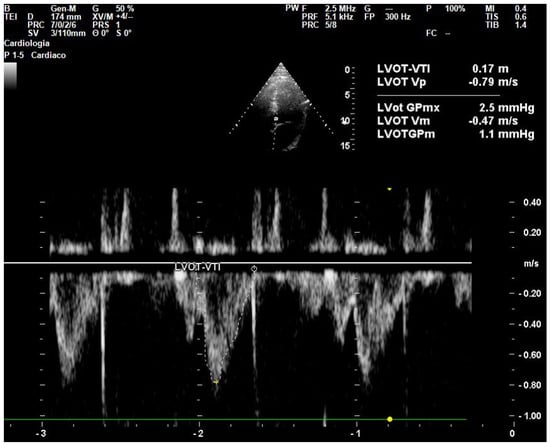

- Wang, J.; Zhou, D.; Gao, Y.; Wu, Z.; Wang, X.; Lv, C. Effect of VTILVOT Variation Rate on the Assessment of Fluid Responsiveness in Septic Shock Patients. Medicine 2020, 99, e22702. [Google Scholar] [CrossRef]

- Parker, C.W.; Kolimas, A.M.; Kotini-Shah, P. Velocity-Time Integral: A Bedside Echocardiography Technique Finding a Place in the Emergency Department. J. Emerg. Med. 2022, 63, 382–388. [Google Scholar] [CrossRef]

| LVOT | Left Ventricular Outflow Tract |

| VTI | Velocity Time Integral |